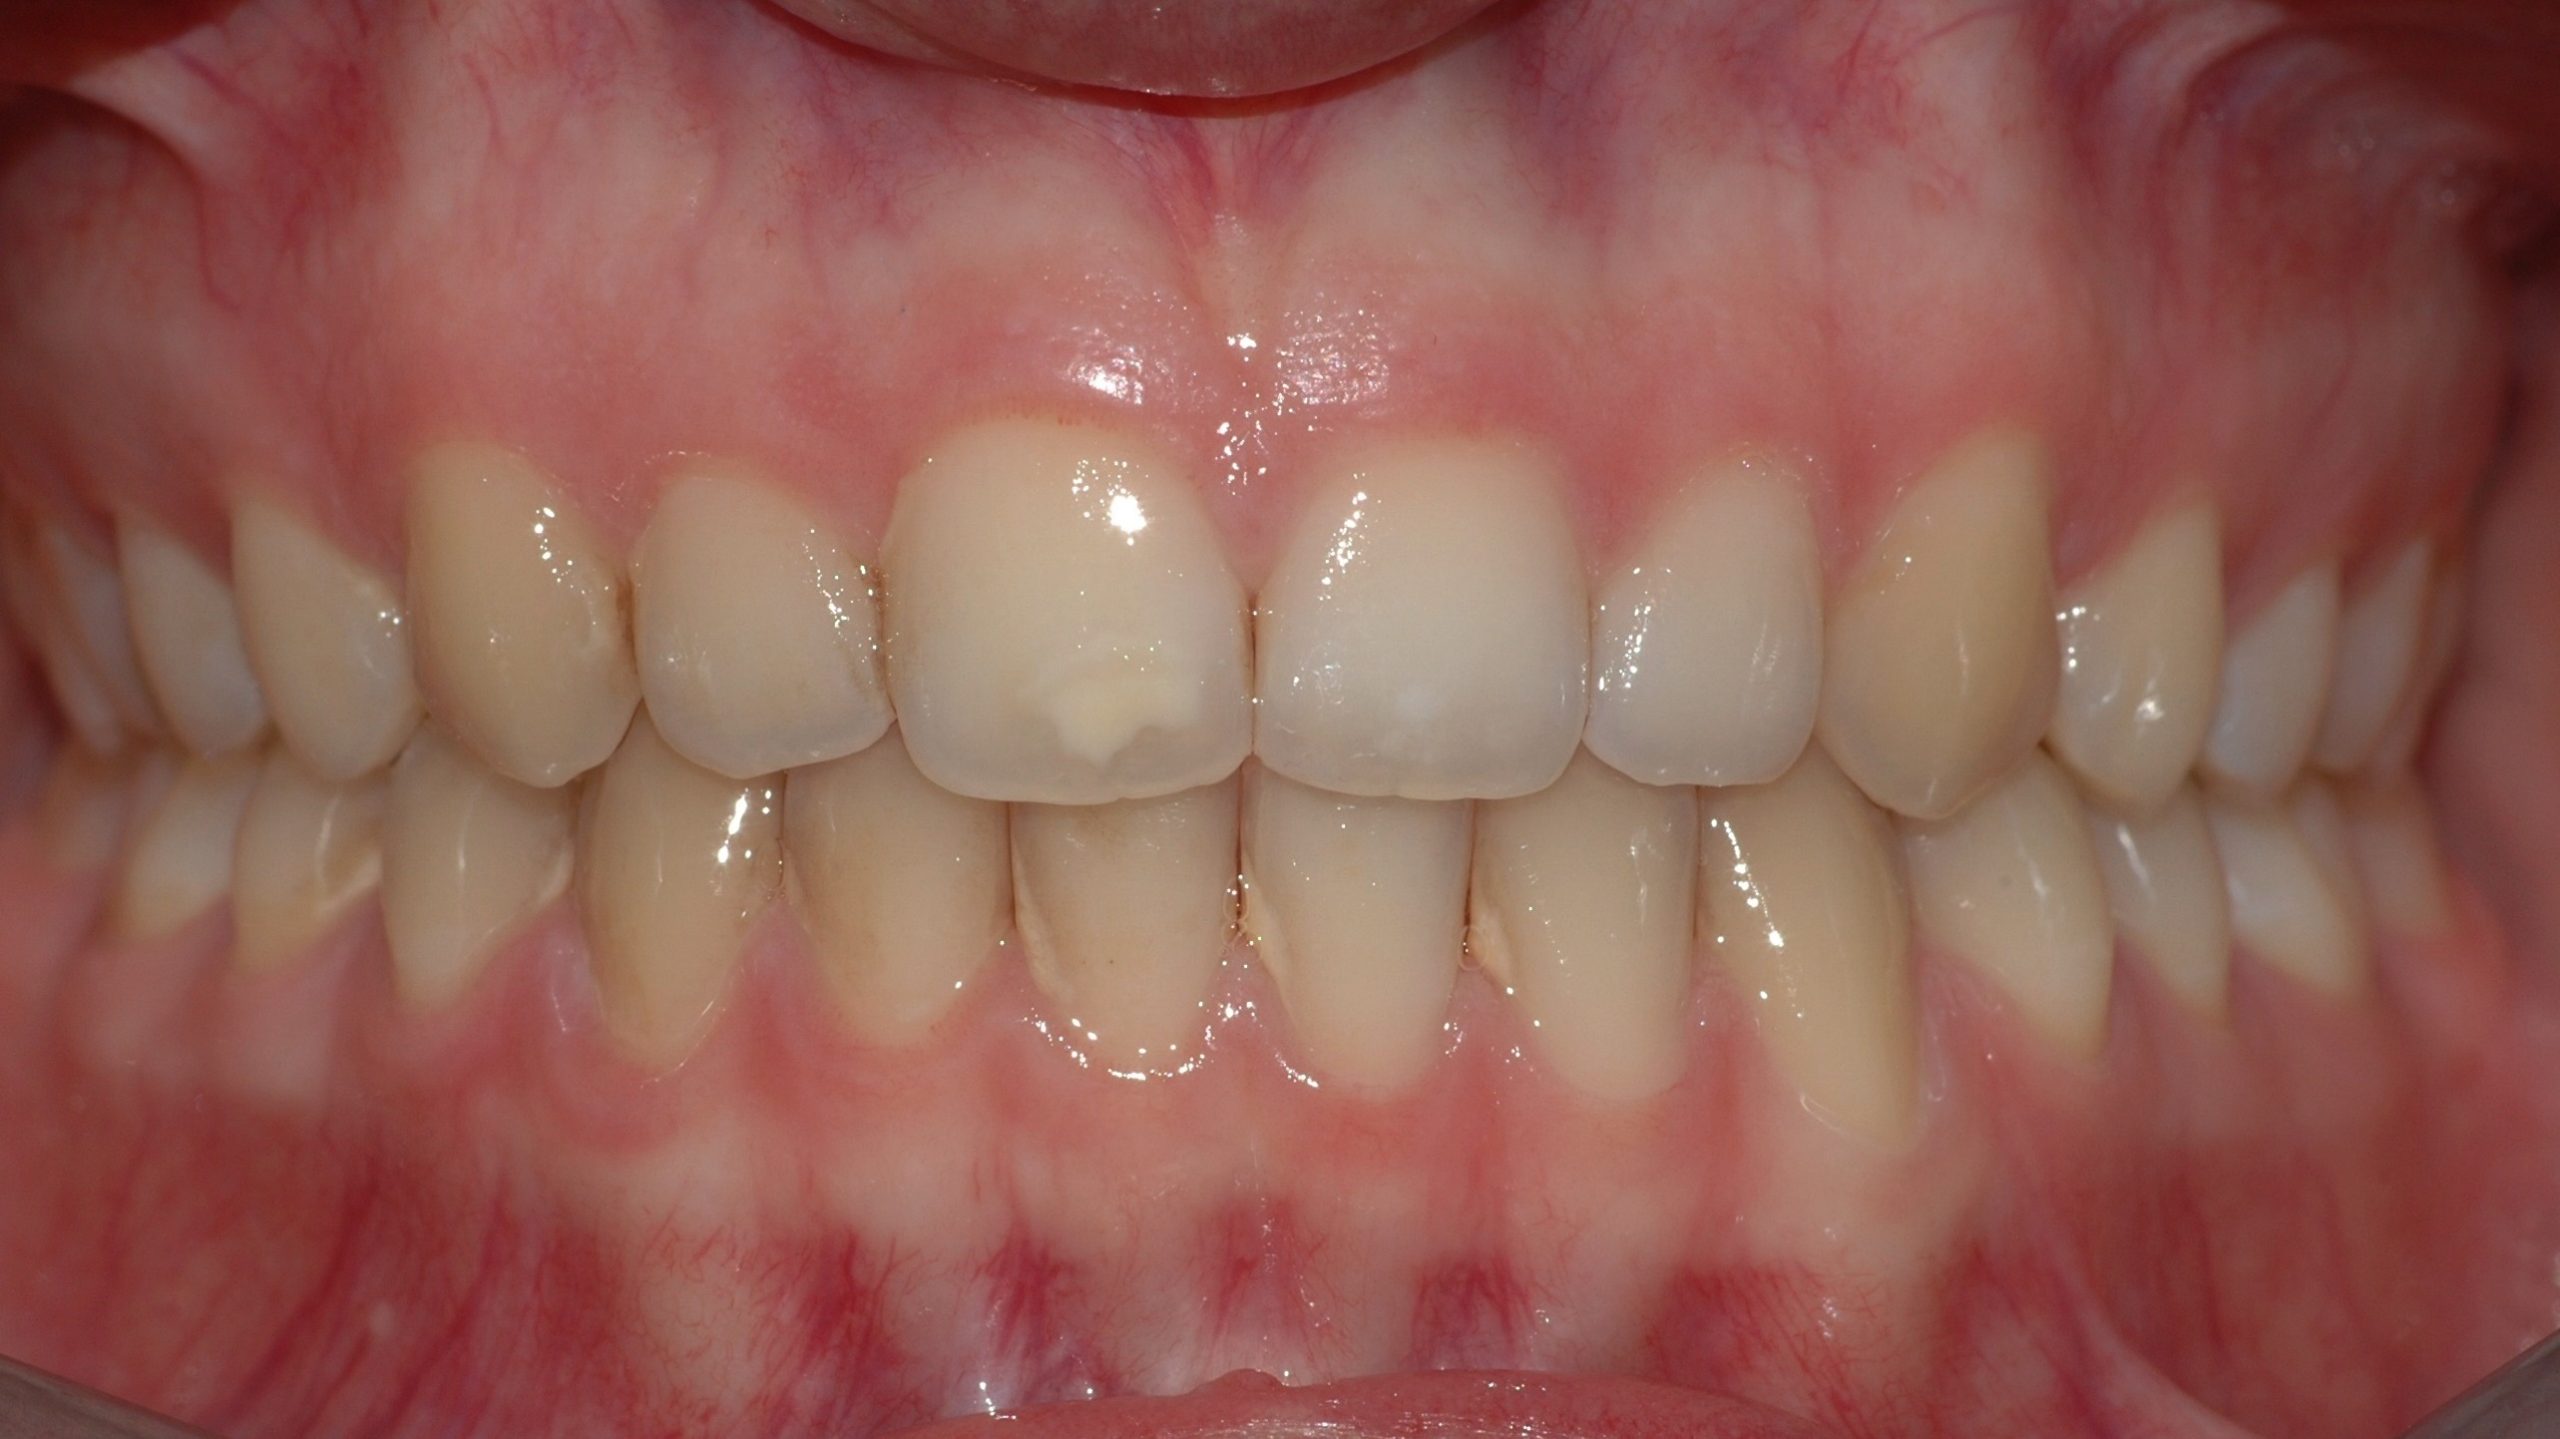

Caso clinico

La paziente si presenta con la richiesta di chiudere il diastema presente tra gli incisivi superiori, sia per motivi estetici, sia a causa di una forte infiammazione gengivale provocata dall’intasamento alimentare (food impaction) nello spazio aperto. In 6 mesi di tempo, il trattamento tramite allineatori, ha chiuso lo spazio e risolto il problema a livello gengivale.

PRIMA

DOPO